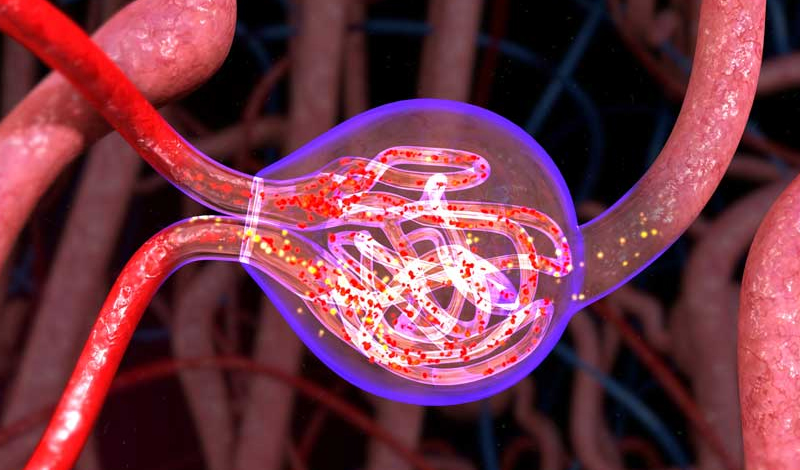

Glomerular Diseases

Glomerular diseases are a group of conditions that damage the glomeruli, the tiny filtering units